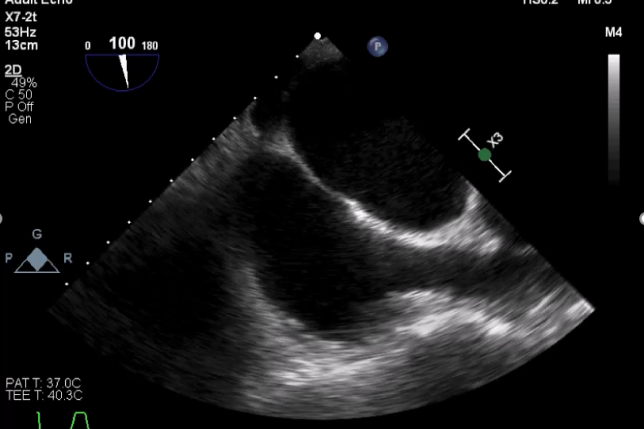

术前TEE

TEE短轴脱垂区域显示(P2、P3区大范围脱垂)

TEE短轴脱垂区域显示(color,血流来源于P2、P3区)

肺静脉收缩期反向血流

平均跨瓣压差:5mmHg